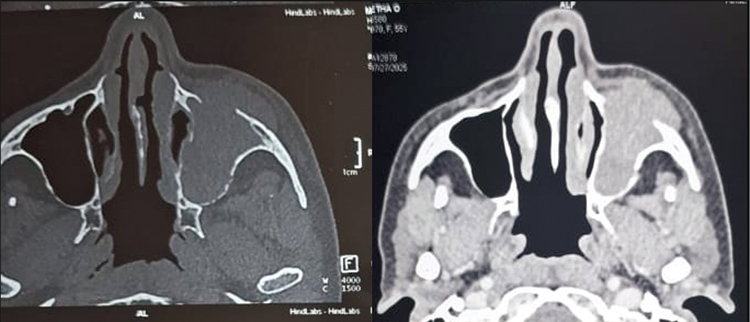

Diagnostic nasal endoscopy showed bulge in left lateral wall obliterating middle meatus with blood stained mucoid discharge in nasal cavity. Contrast enhanced CT and MRI scan of brain (Figure 3) showed heterogeneously enhancing lesion in left maxillary sinus with extension into orbit, nasal cavity, infratemporal fossa, superior alveolar process of maxilla, inferior orbital fissure and infiltration of maxillary division of trigeminal nerve with extensive bone destruction (Figure 2).

Figure 2. Contrast enhanced CT Nose and PNS